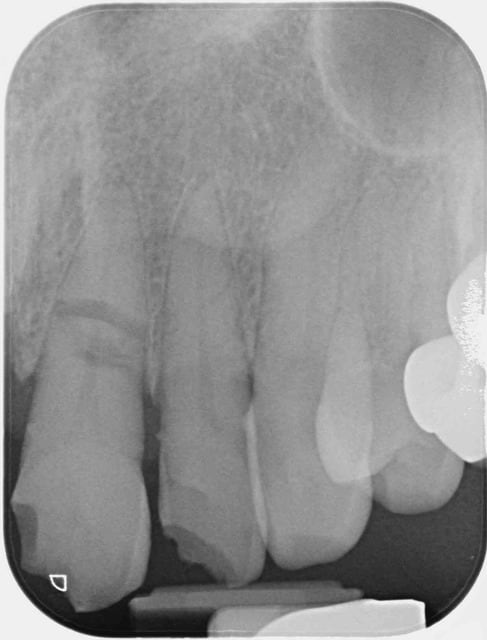

Trauma nhdzdi - Eugenol